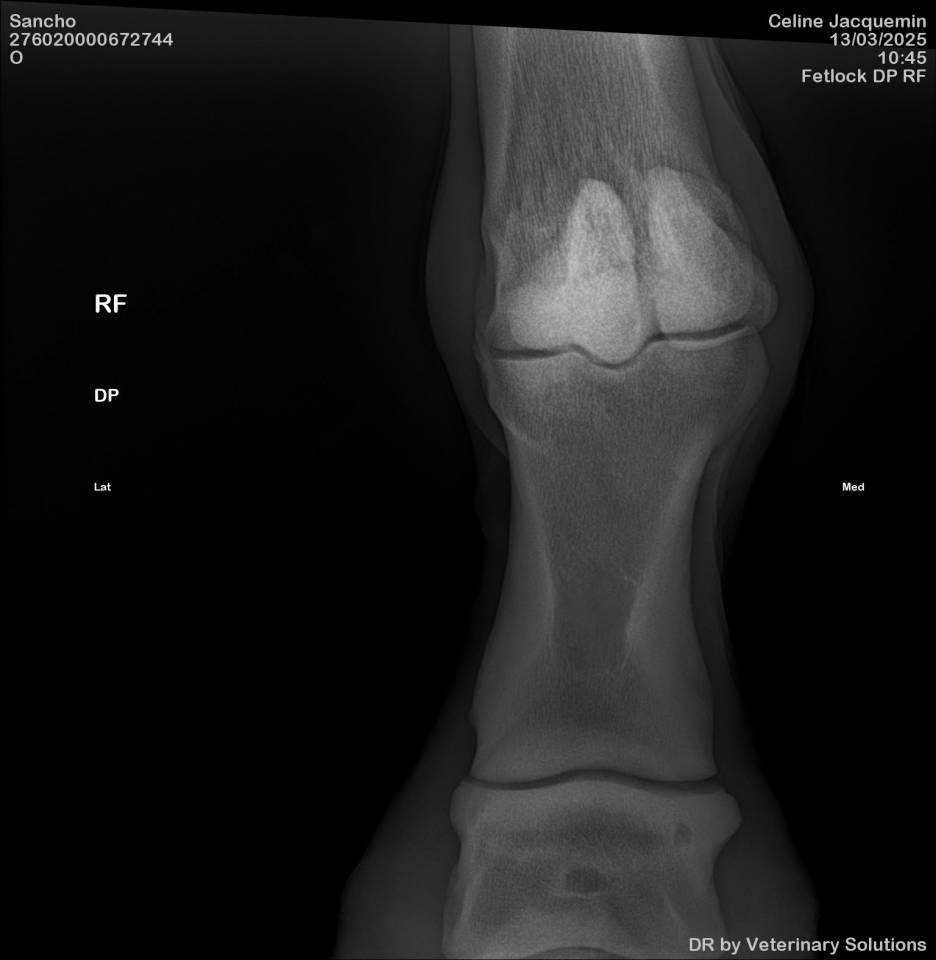

Très bonnes radios sauf kyste à 1 antérieur, qui justifie le prix. Aucun souci clinique.